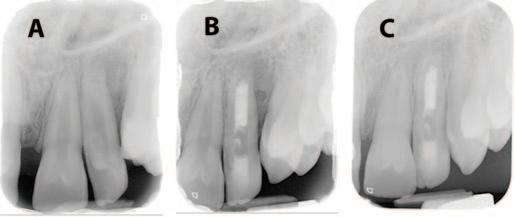

Table 1: Merged-ICDAS visual coronal caries stages.4

Merged-ICDAS score Code Description

Sound (ICDAS 0) 0

Initial caries lesions (ICDAS 1-2) A

No evidence of change in enamel translucency due to caries after plaque removal and air drying

Changes in enamel seen as a caries opacity or visible discolouration (white/brown spot) not consistent with clinical appearance of sound enamel, with no evidence of surface breakdown, no underlying dentine shadowing and no cavitation

Moderate caries lesions (ICDAS 3-4) B3

White/brown spot lesion with localised microcavity/discontinuity, without visible dentine exposure. Best seen after air drying B4 Obviously discoloured dentine visible through apparently intact or microcavitated enamel surface, which originated on the surface being evaluated. Often seen easiest with the tooth surface wet

Extensive caries lesions (ICDAS 5-6) C Obvious visible dentine cavity in opaque/discoloured enamel. A WHO/CPI/PSR probe can gently confirm if the cavity extends into dentine

2. Assess the staging of the coronal carious lesion